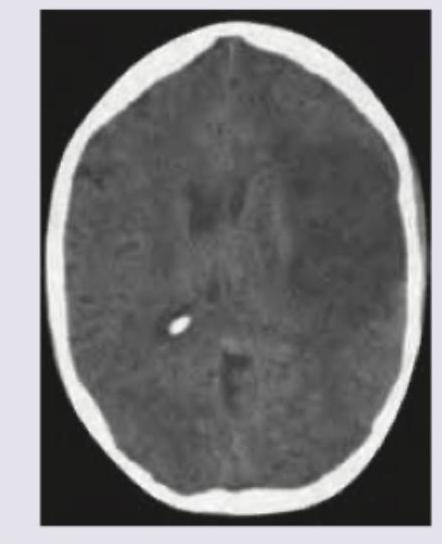

Question 3: A middle-aged patient presents with history of left sided weakness for 2 days. Currently the patient is extremely drowsy and underwent a NCCT brain. Which of the following is the best treatment for this patient? (AIIMS Nov 2017)

Explanation: ***Decompressive surgery*** - The NCCT image shows a **large, well-demarcated hypodensity in the right cerebral hemisphere**, characteristic of a **subacute to chronic ischemic infarct with significant edema and mass effect**. This is evidenced by the effaced sulci, compressed ventricles on the right, and likely midline shift, causing the patient's **drowsiness** and **left-sided weakness**. - Given the patient's **drowsiness** (indicating rising intracranial pressure) and significant mass effect from the large infarct, **decompressive craniectomy** is often a life-saving measure to reduce intractable intracranial pressure and prevent further herniation in cases of malignant middle cerebral artery (MCA) infarction. *Aspirin/Clopidogrel* - These are **antiplatelet medications used for secondary stroke prevention** after an acute ischemic event. - They are not the primary treatment for an **existing large infarct with mass effect and neurological deterioration** (drowsiness), as they do not address the acute intracranial pressure. *Mechanical thrombectomy* - This procedure is indicated for **acute ischemic stroke due to large vessel occlusion**, typically performed within a very narrow time window (usually up to 6-24 hours) from symptom onset. - The patient presents two days after symptom onset, and the CT findings suggest a **subacute to chronic infarct that has completed evolution**, making thrombectomy ineffective and potentially harmful. *Mannitol* - Mannitol is an **osmotic diuretic used to acutely reduce intracranial pressure (ICP)** in situations like cerebral edema. - While it can provide temporary relief, it is often insufficient for profound edema and mass effect from a **large, evolving infarct** that is causing significant neurological decline (drowsiness), and it does not treat the underlying structural issue.